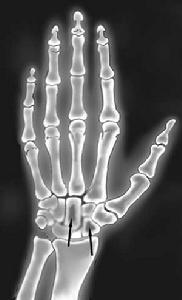

1.X線檢查 X線照片在AL型澱粉樣變中最典型表現為大小不等多發性溶骨性病變常見於顱骨、盆骨、脊柱、肱骨。形狀呈圓形,邊緣清楚其他尚可有骨質疏鬆和病理性骨折食管鋇餐檢查可見反流、蠕動緩慢胃腸鋇餐和鋇灌腸檢查,可見胃腸蠕動緩慢,胃擴張,褶皺減少和胃壁僵硬,十二指腸黏膜呈顆粒狀外觀,顆粒呈白色,直徑1~3mm,少數病人在小腸和大腸內有多發性息肉突起,呈黃色。肺部可見肺紋理增粗或多結節性病變肺門和縱隔淋巴結可腫大。

系統性澱粉樣變性-關節預後: